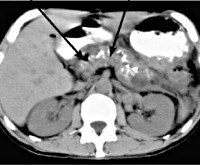

E84.1 Кистозный фиброз с кишечными проявлениями